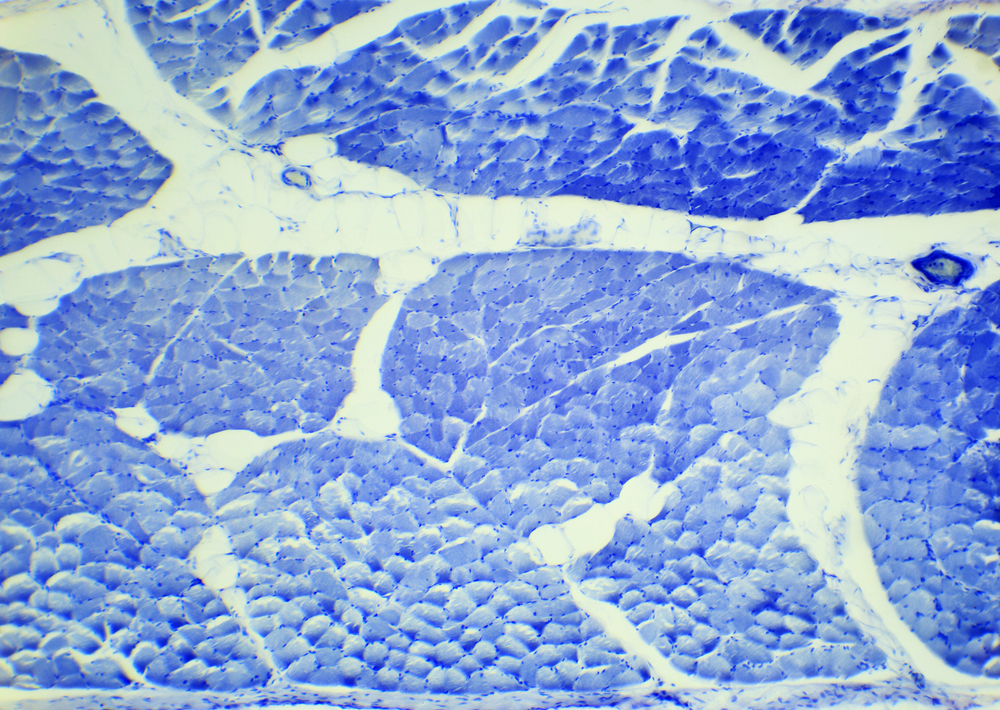

- Biopsy (required for confirmation): A tissue sample is taken and examined to determine cell type and grade. Core needle biopsy is commonly used[1].

Biopsy results help identify the specific subtype of soft tissue sarcoma. Laboratory and genetic testing may detect chromosomal changes or biomarkers that classify the tumor and help guide future care discussions.